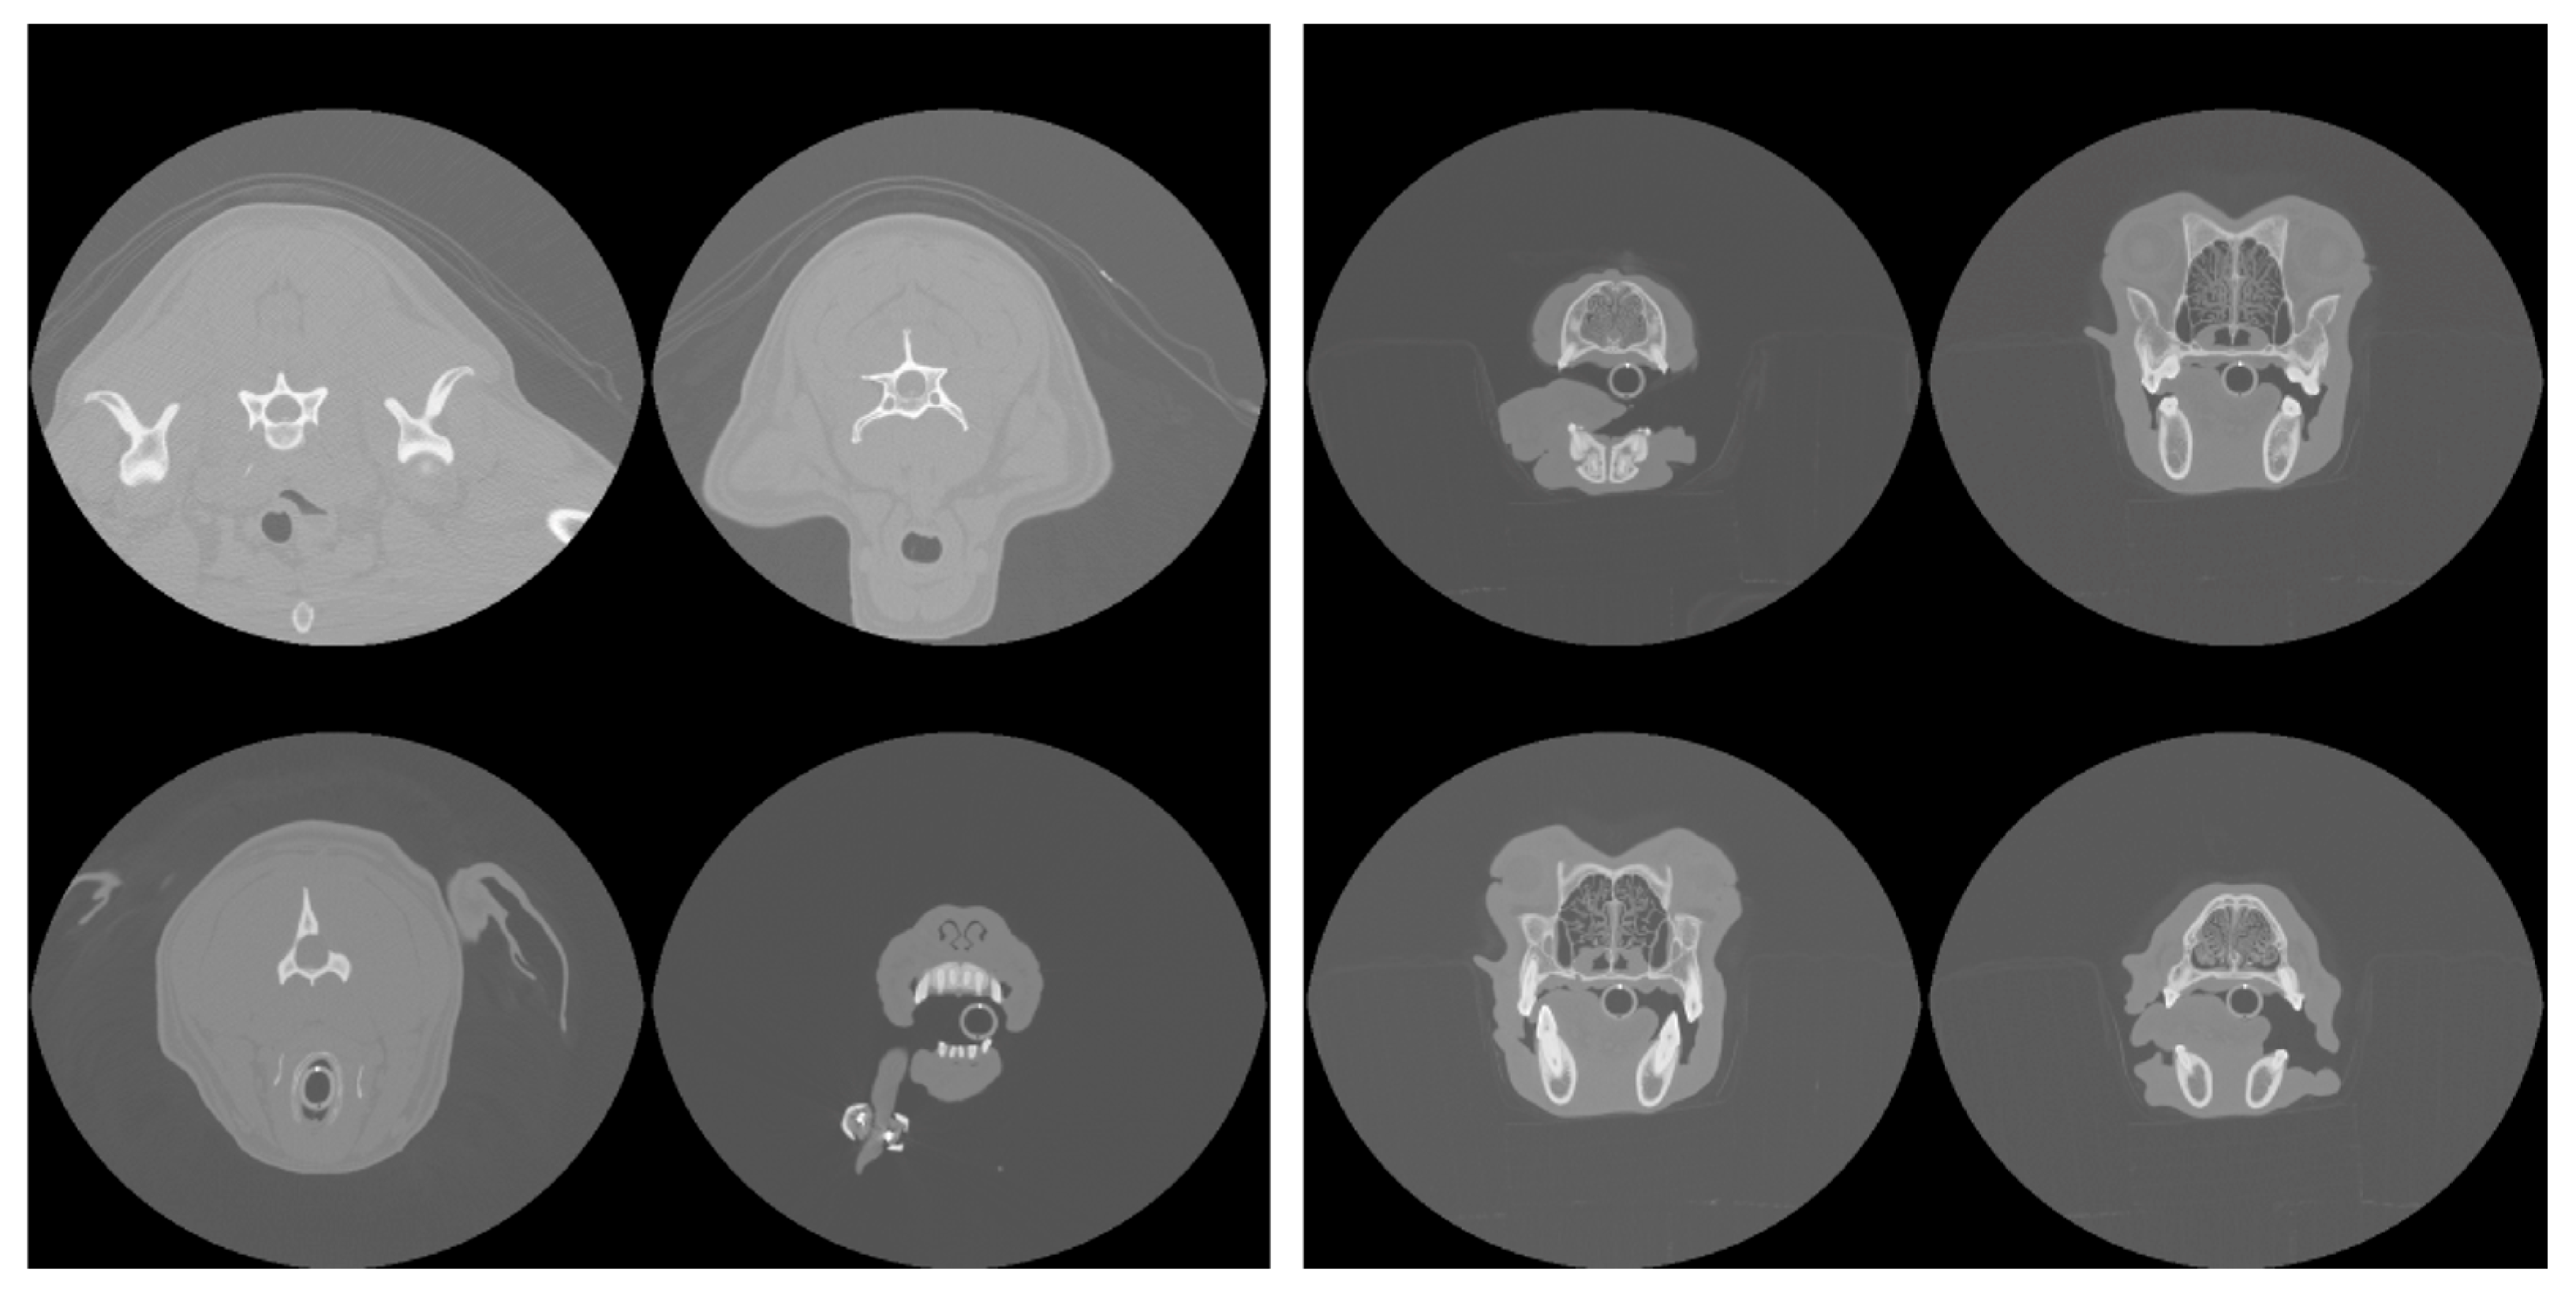

Figure 1 shows an example of the extent of cropping. Both cropped and uncropped slices were created with image dimensions of 96 × 96 pixels and 128 × 128 pixels, reduced from the original dimensions of 512 × 512 pixels of the DICOM scans. Models were trained and tested with different combinations of image resolution and cropping (see next Section 2.3).

The results of segmentation using the ResUNet++ model are shown in Table 2, and an example segmentation is shown in the bottom-right panel of Figure 1. Considering that a Dice coefficient of 1 indicates complete agreement between the predicted and ground truth segmentation masks, the findings reveal the highly accurate identification of nasal cavities by the model. Reliable segmentation is key for the success of the final phase where classification is carried out on these identified areas. Once again, the metrics show that performance degrades slightly when the model is trained and tested on the cropped scans. Figure 2 (middle panel) shows the validation loss and Dice coefficient curves for the segmentation model.

Figure 1. Example of uncropped (top-left) and cropped (top-right) scans projected onto the axial plane. Both cropped and uncropped images were tested in slice selection and segmentation, but only cropped images were used for pathology classification. The bottom-left panel shows the manually defined ground truth mask (highlighted in red) that segments the nasal cavity of the slice shown in the top-right, and the bottom-right panel shows the mask predicted by the segmentation model.